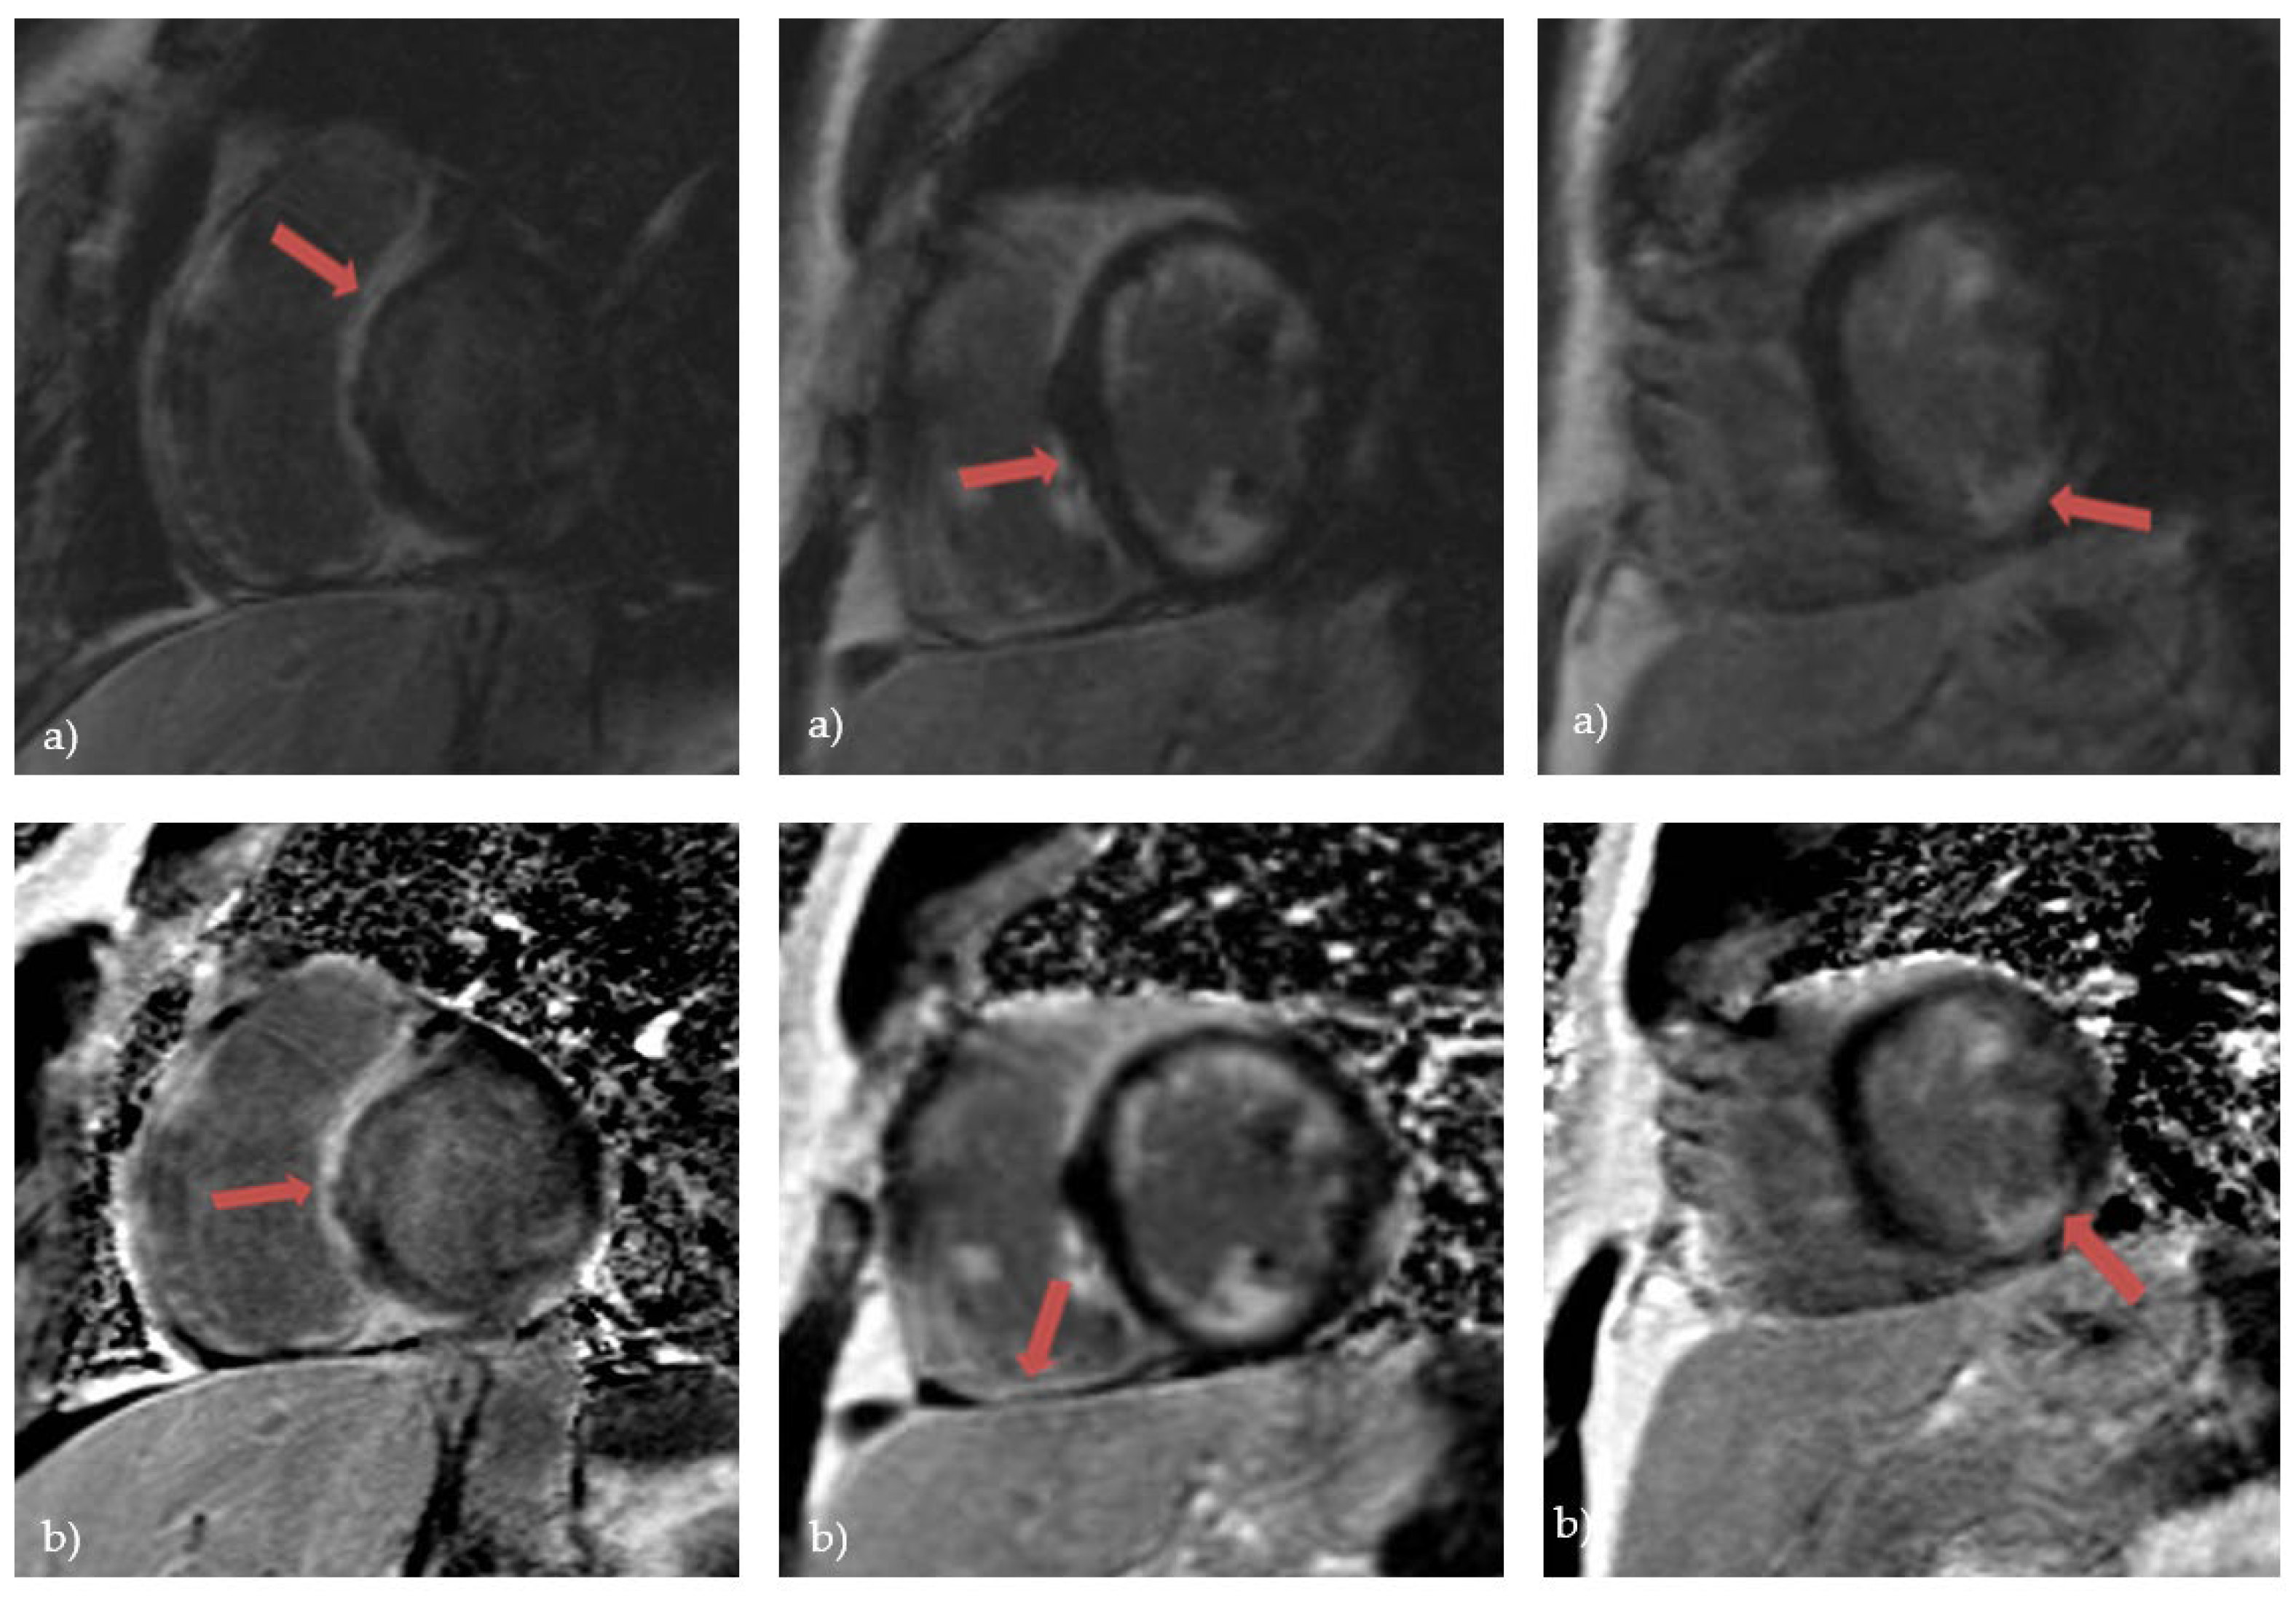

Over the last few years, advanced cardiac imaging which includes CMR has become the preferred way of diagnosing CS due to its non-invasiveness. [19]. It can identify a wide range of myocardial abnormalities in patients with CS, including inflammation, fibrosis, reactive edema, and granulomatous infiltration. Kouranos et al. recently demonstrated that CMR has a significantly greater sensitivity to identify cardiac involvement in relation to echocardiography - 97% vs 27%, respectively [43]. Conversely, in a study that analyzed explanted hearts, CS was histologically confirmed in only 1 of 8 cases presumed to have CS by CMR [72]. The moderately low specificity of CMR had presented the biggest challenge to the diagnosis of CS [73]. However, the specificity of CMR in diagnosing CS increased with the development of novel tissue characterization sequences. This was shown in a large meta-analysis from 2018. that included 649 patients. One group included studies between 2005. and 2011. where the overall sensitivity was 91% and specificity 80%. The second subgroup included studies between 2011. and 2017. where the overall sensitivity was 95% and specificity was even 92% [74]. The hallmark of CS on CMR is the presence of late gadolinium enhancement (LGE) [75]. The main principle of CMR is based on the washout of gadolinium, which is slower in edematous, inflammatory, and scarred tissues, making it visible in CMR’s delayed images [19]. The presence of LGE is not pathognomonic for CS, as it can be seen in a variety of nonischemic cardiomyopathies. However, certain patterns of cardiac involvement are thought to be typical of CS [76]. A systematic review from 2019. which included patients with histologically proven CS observed that the most prevalent pattern of LGE is mid-wall or sub-epicardial enhancement in the septum, lateral wall, and basal ventricular wall (Figure 3). However, there have also been reports of subendocardial or transmural augmentation in other myocardial regions [77].

Figure 3. Cardiac magnetic resonance in a patient with cardiac sarcoidosis: a) LGE MAG study, short axis: LGE in septum and inferior segments; b) LGE PSIR study, short axis: LGE changes in left and right ventricle, predominantly in septal segments (Avanto MRI, Siemens Healthcare GmbH, Erlangen, Germany, 1.5T, CMR Lab University Clinical Hospital Center Bezanijska kosa, Belgrade, Serbia).